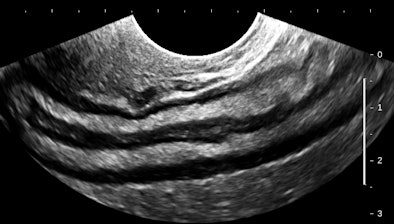

Let's have a look at some selected images from a recent study of a 30-year-old woman with uncertain dates and a positive pregnancy test:

| All images courtesy of Dr. Jason Birnholz. |

There is a intrauterine pregnancy with a (right) corpus luteum with an intact vascular margin. A regular heart rate of 122 beats per minute implies a 6.0-week stage. The Doppler pattern has separate filling and ejection phases. The decidual boundary is thick and well implanted. But there was another unexpected finding when looking at the left ovary:

![]() |

The findings in these views of the distal descending left colon are typical and classic for active ulcerative colitis. The submucosa is thick, reflective, and hyperemic. Some divots can be seen along the mucosa and one transverse section shows a tiny submucosal cyst. What do you think a transabdominal exam would have shown? Would that study have served the best needs of this patient?